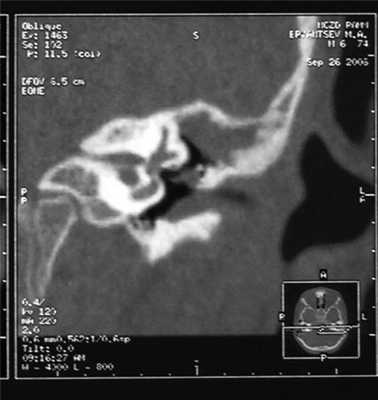

Более того, у 25 (18,1%) человек из общего числа детей с ЭСО были выявлены аттиковые ретракции. У 16 (11,6%) человек определялись глубокие РК, без контролируемого дна. Возраст детей этой группы составлял от 3 до 9 лет. В 3 (2,2%) случаях глубоких РК произошел спонтанный разрыв дна кармана. У 6 (4,3%) детей заподозрена холестеатома надбарабанного пространства, что соответствовало наличию мягкотканного субстрата в аттике при КТ-исследовании височных костей (рис. 4). Рисунок 4. КТ левой височной кости в коротнарной проекции. Наличие мягкотканого субстрата в аттике (1), дислокация слуховых косточек (2) (косвенные признаки холестеатомы). Этим детям проведено хирургическое лечение: эндауральная тимпанотомия с иссечением РК (у 6 детей — холестеатомы аттика), пластикой латеральной стенки аттика и тимпанопластикой.